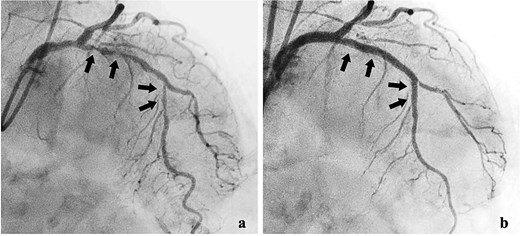

She was transferred to the catheterization laboratory, where coronary and lower extremity angiography revealed 90% stenosis of the left anterior descending artery and tumour blood supply via branches of the deep femoral artery (Figs 2a and 3a).

Coronary angiography findings. (a) Pre-treatment angiography showing 90% stenosis of the left anterior descending artery. (b) Post-treatment angiography showing improved blood flow in the left anterior descending artery after percutaneous coronary intervention.

Dual antiplatelet therapy (DAPT) with aspirin and prasugrel was initiated, followed by PCI with drug-eluting stents (DES) from the left main coronary trunk into the anterior descending artery (Fig. 3b).